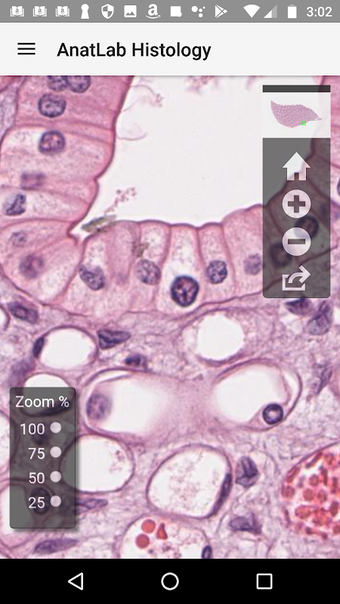

AnatLab Histology es una aplicación gratuita para Android desarrollada por Eolas Technologies Inc. que proporciona a los usuarios imágenes de diapositivas microscópicas de ultra alta resolución. Esta aplicación es una herramienta ideal para estudiantes, profesores, investigadores y el público en general. Con esta aplicación, pueden explorar el paisaje microscópico completo del cuerpo como si estuvieran mirando una colección de diapositivas reales en un microscopio físico. Tiene una función basada en la nube, la aplicación se puede acceder en cualquier dispositivo móvil Android, lo que la hace muy conveniente y accesible.

La aplicación ofrece una colección completa de imágenes de diapositivas microscópicas de histología que se pueden ver en ultra alta resolución. Las imágenes son de calidad excepcional y proporcionan una representación precisa del paisaje microscópico del cuerpo. La aplicación es fácil de usar y navegar, lo que permite a los usuarios explorar diferentes partes del cuerpo con facilidad.